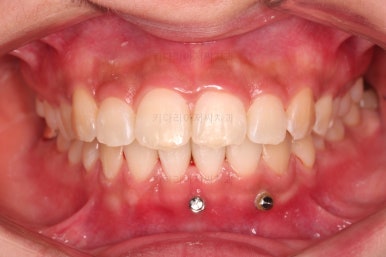

우선 윗니 앞니는 장치를 부착했고요.

아래 앞니는 장치 부착 이전에 아래로 앞니를 내려줄 미니스크류를 식립했습니다.

미니스크류가 단단하게 붙었을 시점에 아래 앞니도 장치를 부착하고요.

과개교합 개선을 위해서 미니스크류까지 힘을 줘서 아래 앞니를 내려줍니다.

이번 환자분이 사용한 장치는 엠파워 클리어라고 하는 자가결찰 세라믹 장치입니다.

일반적으로 클리피씨라고 많이 알고 계시는 장치가 "자가결찰 세라믹" 종류이며 여러 종류 중 엠파워 클리어도 있습니다.

장치 부착 시점의 장치가 보이는 모습과 입매 변화 관찰해 주시고요.